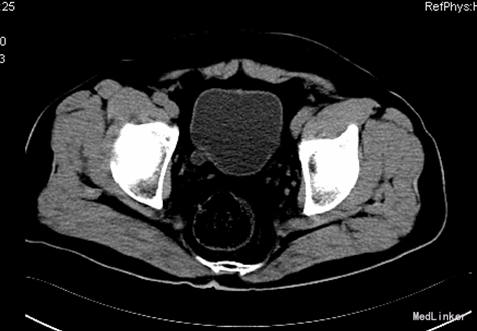

患者,男,55岁8月,因“反复腰背部胀痛6+月”入院。6+月前,患者无明显诱因出现腰背部间歇性胀痛,无发热、恶心、呕吐,无尿频、尿急、尿痛,无肉眼血尿等症状,于当地医院查彩超示“双肾结石”行“左肾结石体外震波碎石”,因“右肾囊肿”而未处理“右肾结石”,术后患者恢复良好,无发热、腹胀、腹痛等不适。此后患者反复出现右侧腰背部不适,未予特殊处理。10+天前,患者自觉右侧腰背部胀痛加重,呈持续性,不伴发热,无肉眼血尿,无尿频、尿急、尿痛等症状,遂于我院门诊行CT示“右肾柱形状结石,右肾积水,右肾萎缩,右侧输尿管下段膀胱入口处结石影”。现患者为进一步诊治入院。

查体:腹部外形正常,全腹柔软,无压痛及反跳痛,腹部未触及包块,肾脏未触及;右肾区叩痛明显,左肾区无叩痛;双侧输尿管压痛点无压痛。 CT:右肾柱形状结石,右肾积水,右肾萎缩,右侧输尿管下段膀胱入口处结石影; 核素肾显像:左肾GFR:30.2ml/min,右肾19.4ml/min。

诊断:1、右肾结石 2、右侧输尿管开口囊肿 3、右侧输尿管下段结石 4、右肾囊肿 5、尿路感染 行右肾碎石术,术中见:右侧输尿管开口处一囊肿,约1.0cm×0.8cm,压迫右侧输尿管开口,随输尿管口喷尿时呈隆起行改变,囊肿内发现一大小约0.5×0.2cm大小结石,右肾盂大量沙粒样结石。